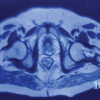

Physical examination revealed that the patient was alert, though her daughter noted increasing forgetfulness, requiring nursing home assistance. Her hands were cool to the touch and displayed a purplish color at room temperature. The left middle finger exhibited necrosis with purulence and gangrene on the radial aspect of the distal phalanx, consistent with digital ulceration. Similar ulcerations were noted on the ring finger, indicating Raynaud’s phenomenon. MRI findings demonstrated subcutaneous edema around the middle and proximal phalanges of the fingers and evidence of flexor tenosynovitis in the middle finger. Previous cultures identified Corynebacterium accolens in the paronychial infection. The patient was scheduled for debridement surgery and diagnostic tests due to a high suspicion of undiagnosed systemic sclerosis. Tests included rheumatoid factor, ANA, HLA-B27 antibody testing, and others for pre-operative planning. The patient had a positive anticentromere antibody (>8 AI) and a positive ANA screen, along with Vitamin D deficiency. Radiographs revealed osteolysis of the distal phalanx, consistent with osteomyelitis, and MRI confirmed bone marrow edema and flexor tenosynovitis. During surgery, the patient underwent exploration of the necrotic digital ulcer and debridement of the radial aspect of the distal phalanx. C-arm fluoroscopy confirmed osteolysis of the phalanx (Fig. 1). Irrigation and debridement of skin, subcutaneous tissue, and bone were performed, followed by partial ostectomy (Fig. 1). Microscopic analysis revealed acute osteomyelitis with fibrosis, clusters of neutrophils, and necrotic debris. No abnormal cells were detected. Further culturing confirmed C. accolens, with Gram stain showing Gram-positive rods. Following the procedure, the patient was treated with doxycycline, Vitamin D3, and vasodilators. A 2-week follow-up showed intolerance to topical nitroglycerin, which was switched to topical nifedipine and pentoxifylline. By the 4-week follow-up, the patient was tolerating treatment, with the wound healing well. Antibiotics were discontinued at 3 months, and 2 months post-treatment; the patient showed no signs of infection (Fig. 2).